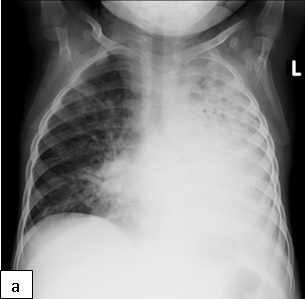

Characteristic chest radiographic findings of LIP include bilateral, diffuse, reticulonodular infiltrates that are more prominent in the lower lobes, and bilateral hilar adenopathy. Distinguishing LIP from PTB or miliary TB can be a challenge.